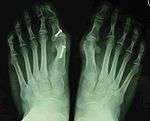

Syndesmosis procedure addresses specifically the two fundamental problems of metatarsus primus varus deformity that gives rise to the bunion deformity. They are leaning and instability of the first metatarsal bone . Syndesmosis procedure uprights the leaning first metatarsal bone with strong binding sutures between it and the second metatarsal bone (Fig. 2) and then also stabilizes it uniquely by creating a fibrous connecting bridge between these two bones (Fig. 3,4). First metatarsal bone can be readily realigned is because by definition of the metatarsus primus varus deformity its first metatarsal is abnormally loose and mobile.